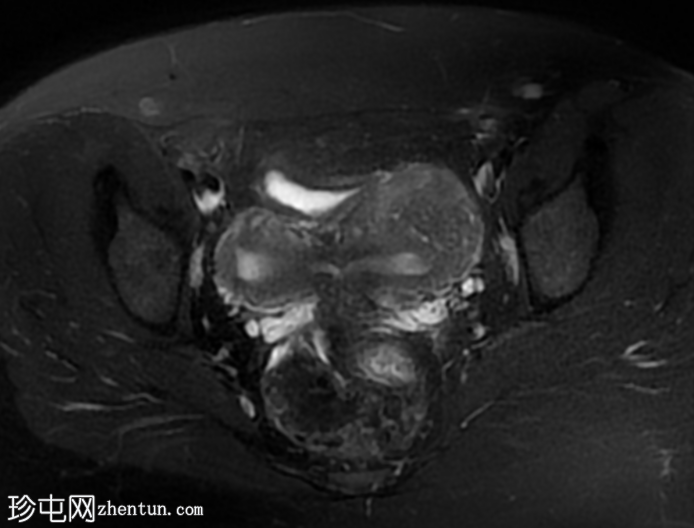

轴位

T2加权像

5.png

双角子宫,有两个子宫角和一个宫颈(单颈双角子宫)

右角正常,分区解剖结构正常,无肌层病变

左角局灶性前壁腺肌症,前壁交界区边界不清,肌层内可见多个高信号灶

两个小的间质性肌瘤和一个大的浆膜下肌瘤

宫颈纳博氏囊肿

该病例表现为双角子宫单宫颈(双角单颈子宫),左侧单侧局灶性子宫角腺肌症,以及多发性子宫肌瘤。